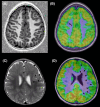

Focal cortical dysplasia (FCD) is a common cause of drug-resistant focal epilepsy in children and young adults and is often surgically remediable. The genetics of FCD are increasingly understood due to the ability to perform genomic testing including deep sequencing of resected FCD tissue specimens. There is clear evidence that FCD type II occurs secondary to both germline and somatic mTOR pathway variants, while emerging literature supports the role of SLC35A2, a glycosylation gene, in mild malformation of cortical development with oligodendroglial hyperplasia and epilepsy (MOGHE). Herein, we provide a review of FCDs focusing on their clinical phenotypes, genetic basis, and management considerations when performing genetic testing in this patient group.